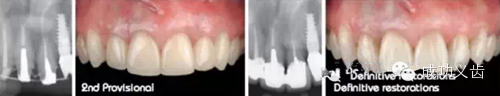

图1.延期种植1,2007年种植修复刚刚完成时的照片。

图2.延期种植2,2014年不论是从照片还是X线上,都显示出种植周围软硬组织稳定,颜色粉嫩!